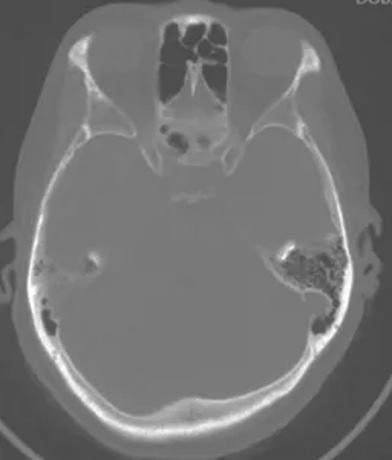

CT bone window of the skull base

No significant enlargement of the right optic canal